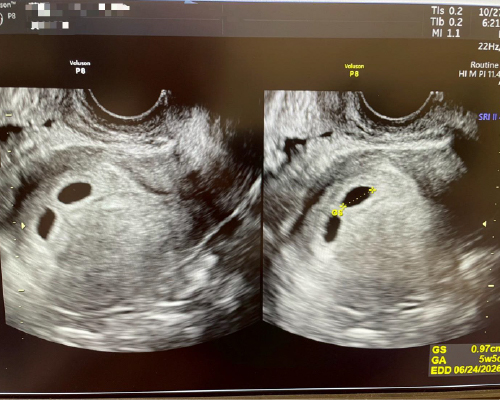

36歲AMH 3.6

第一次取卵

第一次植入

以長效排卵針Elonva 刺激排卵

取卵24#. MII 16#. 2PN 11#.

冷凍囊胚11#

植入4AB/4BB 2#

今天5+周超音波有看到兩個眼睛👀

期望胚胎乖乖長大